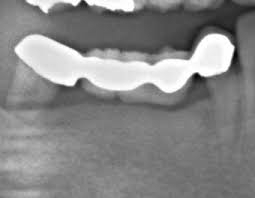

大型の欠損においては部分入れ歯を推奨することもありますが、両サイドの大臼歯がない場合(両側遊離端欠損)には入れ歯を入れることで欠損が拡大していきやすくなります。

![]() |

部分入れ歯は柔らかい粘膜(歯肉)の上に乗っているので、噛むたびに沈みます。

特に後方に自分の歯が残っていない場合にはその沈下量は非常に大きくなります。

するとクラスプが今残っている一番奥の歯を引き抜く力をかけ、歯を失い、また一つ前の歯にかけて…という悪循環に陥ります。

このような場合にもインプラントは非常に有効なものになります。

こういった場合には部分入れ歯の最後方歯に相当する部位にインプラント体(ネジの部分、フィクスチャ)のみを埋入し、その上に人工歯ではなく金属のフタのようなものを装着し、歯茎から頭を出させておいて、その上に部分入れ歯が乗るようにする、インプラントサポートデンチャー(インプラントが支える入れ歯)という治療法が有効になります。

インプラントは異常がなければ力がかかっても全く揺れたり動いたりしません。後方に歯がない部分入れ歯は噛んだとき粘膜(歯肉)を押して沈むことで様々な弊害をおこすものなので、インプラントとそこに装着された金属のフタで入れ歯が沈み込まないように支えてあげることができるのです。